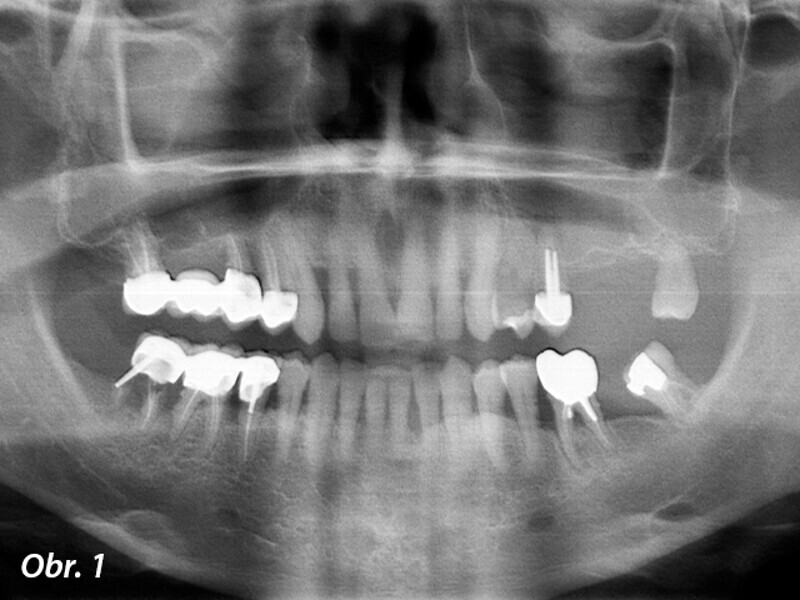

Rehabilitace unilaterální maxilární bezzubosti